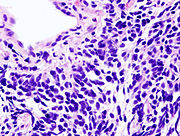

Small cell lung carcinoma (SCLC)

Small cell lung carcinoma (SCLC, also called "oat cell carcinoma") is less common. It tends to arise in the larger airways (primary and secondary bronchi) and grows rapidly, becoming quite large. The "oat" cell contains dense neurosecretory granules ( vesicles containing neuroendocrine hormones) which give this an endocrine/paraneoplastic syndrome association. While initially more sensitive to chemotherapy, it ultimately carries a worse prognosis and is often metastatic at presentation. Small cell lung cancers are divided into Limited stage and Extensive stage disease. This type of lung cancer is strongly associated with smoking.